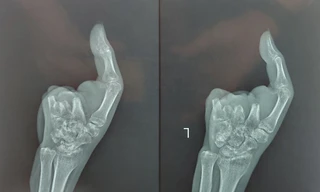

TPO - Sơ ý trong lúc làm việc, người phụ nữ bị máy xay thịt cuốn nát bàn tay trái. Các bác sĩ đã thực hiện cuộc phẫu thuật chuyển 2 ngón của bàn chân lên làm ngón tay giúp bệnh nhân thực hiện được chức năng cầm nắm.